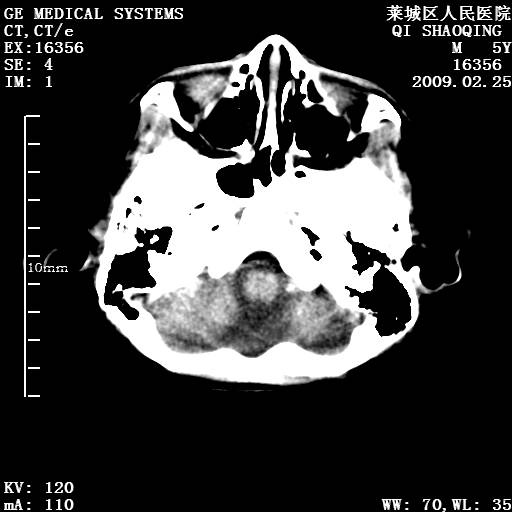

以下是引用wangzhengyuan在2009-2-28 10:22:00的发言:[br]甲状旁腺功能减退引起的脑改变.

以下是引用zsl6918在2009-2-28 10:17:00的发言:[br]首先考虑甲状旁腺功能低下所致,可结合实验室检查明确.另外需除外先天性宫内感染所致.

以下是引用余辉在2009-3-1 9:35:00的发言:[br]患者明显的肢体及智力改变,不支持fahr病,多考虑甲旁低,有可能伴有甲低(呆小症).进一步检查。